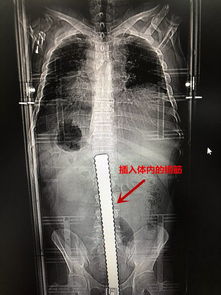

食管癌-吞咽梗阻感半年,胃镜发现食管全周狭窄

引言 食管癌是我国高发的消化道恶性肿瘤之一,其典型临床症状常表现为进行性吞咽困难、异物感及胸骨后疼痛。当患者出现长达半年的吞咽梗阻感,并通过胃镜检查发现食管全周性狭窄时,这通常提示病变已进入中晚期阶段,临床处理面临严峻挑战。全周性狭窄意味着肿瘤已沿食管壁环形浸润生长,严重阻碍食团通过,并显著影响患者的生活质量与营养状况。本文旨在系统阐述此类病例的病理机制、诊...